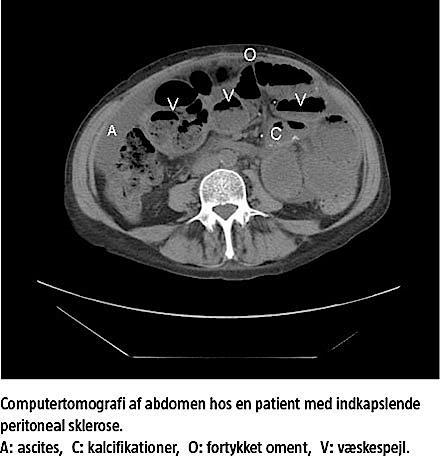

Trods konservativ behandling med parenteral ernæring forværredes patientens tilstand. En CT af abdomen viste nu inkomplet tyndtarmsileus og desuden kalcifikationer i peritoneum viscerale. Man fik mistanke om EPS og foretog eksplorativ laparotomi, hvorved der blev fundet adhærencer og cementering af tyndtarmen, hvilket er karakteristisk for EPS. Der blev sikret tarmpassage ved anlæggelse af en side-to-side-enteroanastomose.

1) klinik: ileus/subileus, vægttab, hæmoperitoneum, sterile eller recurrente peritonitter, 2) radiologi: CT af abdomen viser peritoneal fortykkelse med kalcifikationer samt ændring af tarmvæg og -lumen, 3) histologi: Mulige markører er inflammation, fibrinaflejring, submesotelial compactatykkelse, kalcifikationer og karforandringer, og 4) laparoskopi/laparotomi: indkapsling af de intraabdominale organer i fibrotisk peritoneum [1, 4].